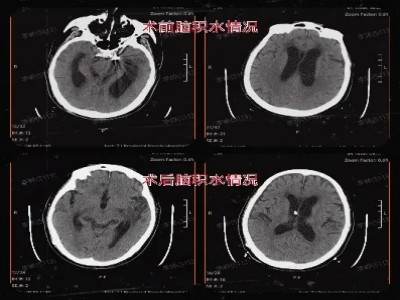

手术前后头颅CT

叶主任迅速组织了神经外科专家团队进行了会诊。经过充分讨论和评估,神经外科高法梁副主任医师精心规划了手术方案,为金大爷实施了“脑室-腹腔分流术”。脑脊液得到了有效的引流,为金大爷的后续康复扫清了障碍。